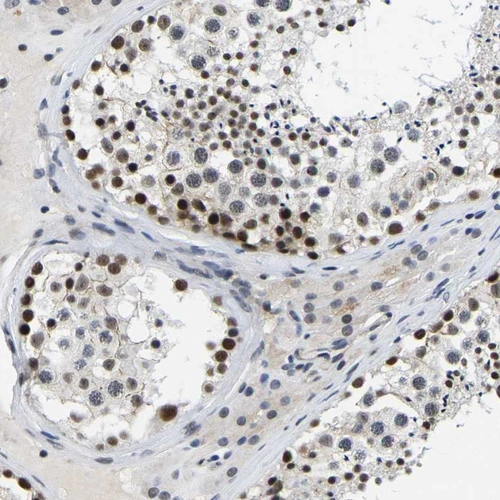

Immunohistochemical staining of human testis shows strong nuclear positivity in cells in seminiferous ducts.